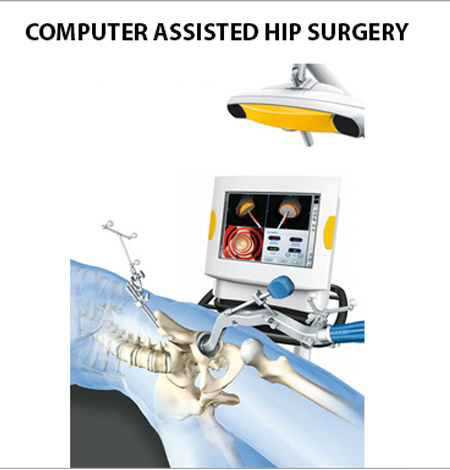

Computer-assisted (Minimal Invasive) Hip Replacement

Well -aligned and balanced hip replacements during a surgery go a long way in making the patient feel healthy and strong about their mobility. In computer-assisted surgery, a robot acts as an extended arm to the surgeon. The robotics help surgeons operate more efficiently through a smaller incision.

It not only makes the process more efficient but also considerably shortens hospital stay and minimizes recovery time. Dr D K Das, an expertise in orthopaedic surgery is among the very few surgeons who have advanced training in computer navigation surgery.